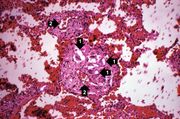

| 03:39, 19 August 2013 | IPLab3Tuberculosis3.jpg (file) | 77 KB | Seung Park | This is a photomicrograph of a tuberculosis granuloma. Note the central core of caseation necrosis (1) encircled by a rim of epithelioid macrophages and lymphocytes (2). Langhans’ type multinucleated giant cells are also present although they are dif... | 1 | |